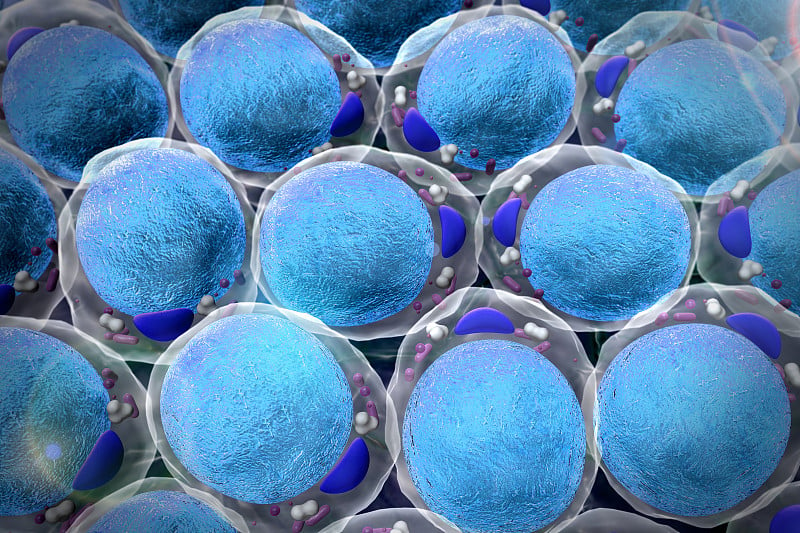

脂肪细胞场详情

胆固醇、脂肪细胞详情

脂肪细胞的3D插图详情

脂肪细胞,病毒详情

病毒和脂肪细胞详情